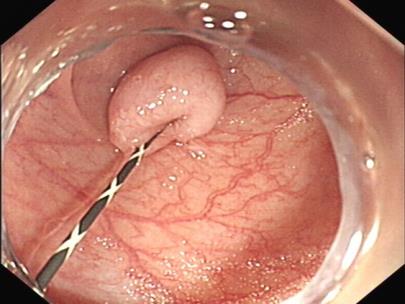

摘要:目的 比较内镜下套扎手术与外科痔切除术对内痔的治疗价值。方法 选择2023年2月-2025年4月该院收治的340例内痔患者,根据治疗方法分为两组,行外科痔切除术的160例患者为对照组,行内镜下套扎手术的180例患者为观察组,比较两组患者手术相关指标,评估术后肛门疼痛情况,检测手术前后血清炎症因子、肛门功能、肛肠动力学指标和肛门狭窄程度,统计并发症情况。结果 观察组手术时间明显短于对照组,术中出血量明显少于对照组,治疗费用明显低于对照组,差异均有统计学意义(P < 0.05)。术后1和7 d,观察组疼痛视觉模拟评分法(VAS)评分明显低于对照组,差异有统计学意义(P < 0.05);术后1个月,观察组血清炎症因子水平明显低于对照组,差异有统计学意义(P < 0.05);术后1个月,观察组肛门功能Kelly量表评分明显高于对照组,差异有统计学意义(P < 0.05);术后1个月,两组患者肛肠动力学指标水平比较,差异有统计学意义(P < 0.05);观察组并发症发生率和肛门狭窄率明显较低(P < 0.05)。结论 内镜下套扎手术与外科痔切除术均可用于内痔治疗中,但与后者相比,前者在改善血清炎症因子、肛门功能、术后疼痛感方面效果更佳,还可缩短手术时间,减少术中出血量,减轻经济负担。